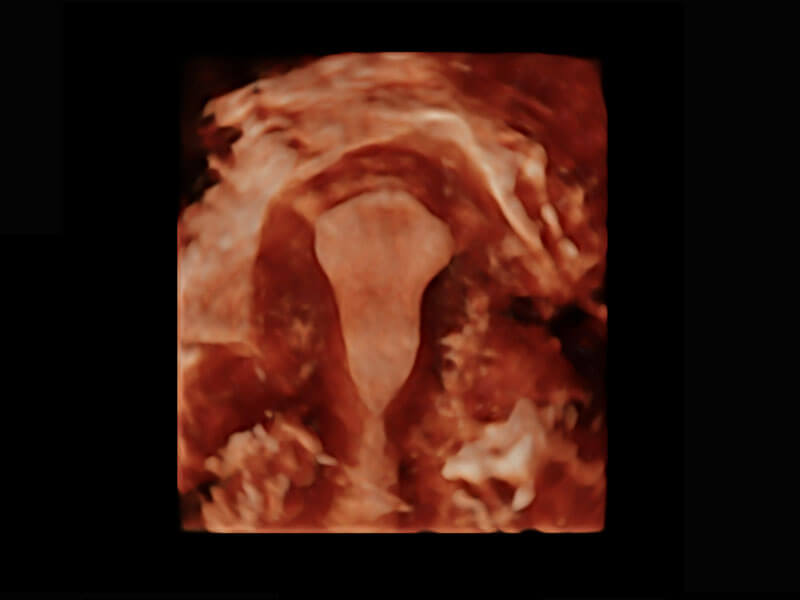

腔内三维-光影成像

腔内三维-宫内节育器